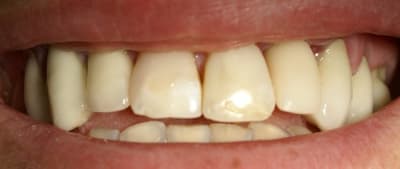

Tout repose sur le fait de poser les bonnes indications. S'aventurer et aventurer le patient quand on doit poser un implant, reconstruire un pan osseux vetibulaire, gérer les tissus mous en même temps, très peu pour moi. Quand je fais une implantation immédiate et mise en charge immédiate c'est que je suis relativement sûr de moi. Sinon, je diffère la mise en charge. Certes quelques mois de plus de cicatrisation mais une sérénité certaine.

Dans ce cas là, c'était une implantation post extractionnelle immédiate et une mise en esthétique immediate.

Ce cas est limite et aurait pu être traité en deux temps mais bon, j'ai opté pour y aller franco...

La seamine prochaine je vous montrerai la finition céramique.